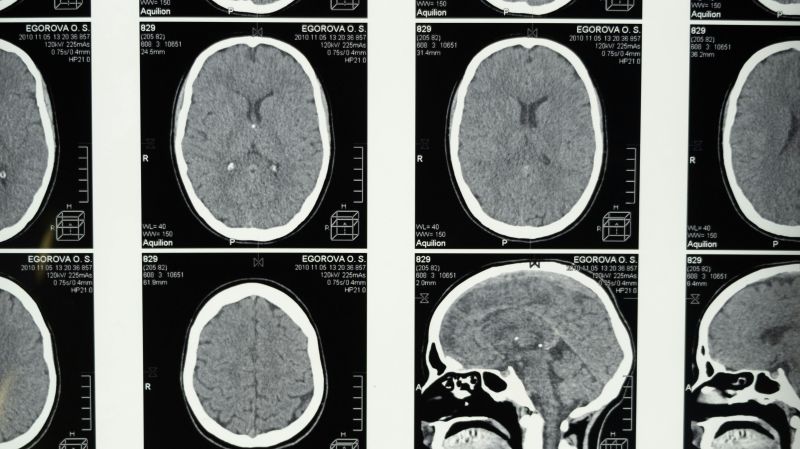

Human brains contain approximately 7 grams of plastic (equivalent to several bottle caps).

Brain samples from 2024 showed 50% MORE microplastics than samples from 2016.

Across numerous animal studies, microplastics consistently impair memory, learning, and social behavior - with concerning parallels to dementia. According to new research, microplastic concentrations were 3 to 5 times higher in the brains of patients with dementia, compared to cognitively normal brains. It’s not clear whether microplastics may cause or contribute to dementia, nor whether dementia-induced changes to the brain might allow more microplastics to enter.